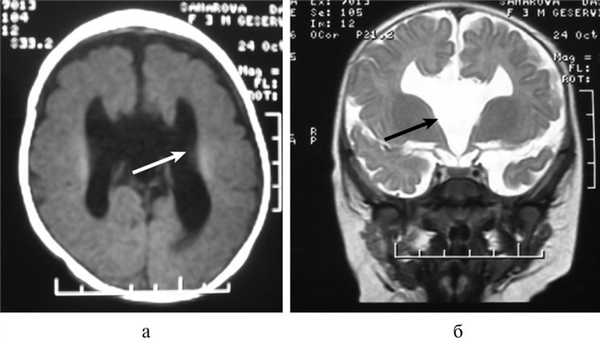

При визуализационных методах - нейросонографии (НСГ), рентгеновской компьютерной томографии (КТ), магнитно-резонансной томографии (МРТ) головного мозга - патогномоничным признаком синдрома Айкарди является агенезия мозолистого тела. Выделяют полную агенезию мозолистого тела, при которой отсутствуют все комиссуральные структуры вместе с фрагментами прозрачной перегородки, и частичную агенезию, которая в свою очередь подразделяется на агенезию ростральных и каудальных отделов мозолистого тела [29]. Чаще встречается агенезия каудальных отделов мозолистого тела, которая может сочетаться с изолированной дилатацией задних отделов боковых желудочков - кольпоцефалией. КТ-признаки агенезии мозолистого тела включают визуализацию межполушарной кисты, смещение вверх расширенного III желудочка и специфическое изменение формы тел боковых желудочков с увеличением расстояния между ними в виде симптома «ухвата» [7, 31]. Определяется расширение задних рогов боковых желудочков, своеобразный U-образный характер передних (фронтальных) рогов, удлиненная форма отверстия Монро. Кроме того, часто выявляются признаки атрофии вещества головного мозга в виде углубления и расширения конвекситальных борозд, расширения межполушарной и латеральной щелей, множественные пороки развития головного мозга.

Постнатальная ультразвуковая картина АМТ характеризуется отсутствием изображения МТ; исчезновением нормальной архитектоники борозд и извилин в сагиттальной плоскости сканирования; веерообразным отхождением борозд от крыши III желудочка; широким расположением боковых желудочков с изменением ориентации передних рогов в коронарных плоскостях и смещением вверх или расширением III желудочка. На К.Т. определяются параллельный ход и увеличение расстояния между телами боковых желудочков, расширение задних рогов и преддверий боковых желудочков (кольпоцефалия) [11].

Важной находкой при АМТ на МРТ является параллельная ориентация тел боковых желудочков по отношению друг к другу (рис. 4, а), расширенные фронтальные отделы желудочков, так называемый «симптом ухвата».

Рис. 4. МРТ головного мозга больной К., 4 года. АМТ. Аксиальная проекция: а — аномальная параллельная ориентация тел боковых желудочков по отношению друг к другу (стрелка); б — фронтальное сечение: деформация передних и задних рогов боковых желудочков, своеобразный U-образный характер фронтальных отделов боковых желудочков (стрелка).